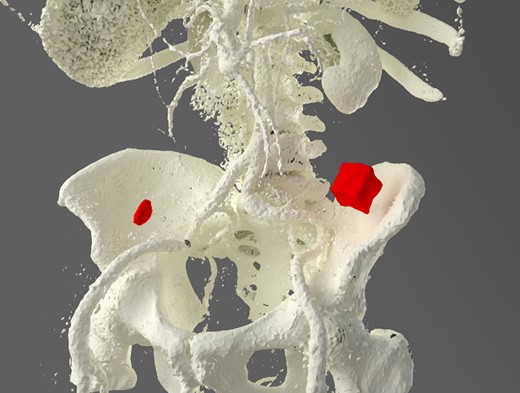

A 92-year male, with no significant co-morbidities apart from peptic ulcers, was admitted with 6 days of obstination. On examination he was dehydrated, with a hugely distended abdomen but no signs of peritonitis. Blood showed features of dehydration and plain abdominal X-ray demonstrated both small and large bowel dilatation, but no obvious causal pathology. A contrast-enhanced computed tomography scan revealed a 2.5-cm partially calcified gallstone impacted at the descending colon-sigmoid junction (Fig. 1). There was no stricture or diverticular disease distal to the stone. A cholecysto-colic fistula could be seen (Fig. 2), with a further smaller gallstone in the caecum (Fig. 3). The offending gallstone could be seen incidentally in the gallbladder on imaging 3 years previously (Fig. 4).

Large gallstone impacted in the descending colon-sigmoid junction, causing large bowel obstruction proximally.

CT reconstruction showing the impacted gallstone and a smaller incidental gallstone in the caecum.